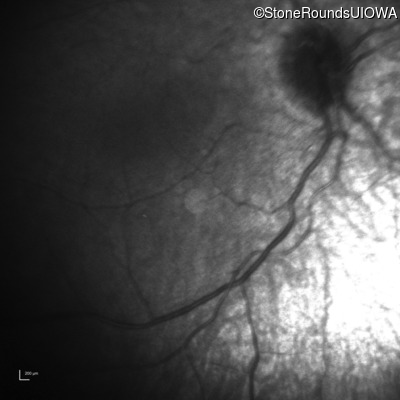

Infrared Fundus Photograph - Left -

No Light Perception

Exemplar

Expanded OCT Stack

×